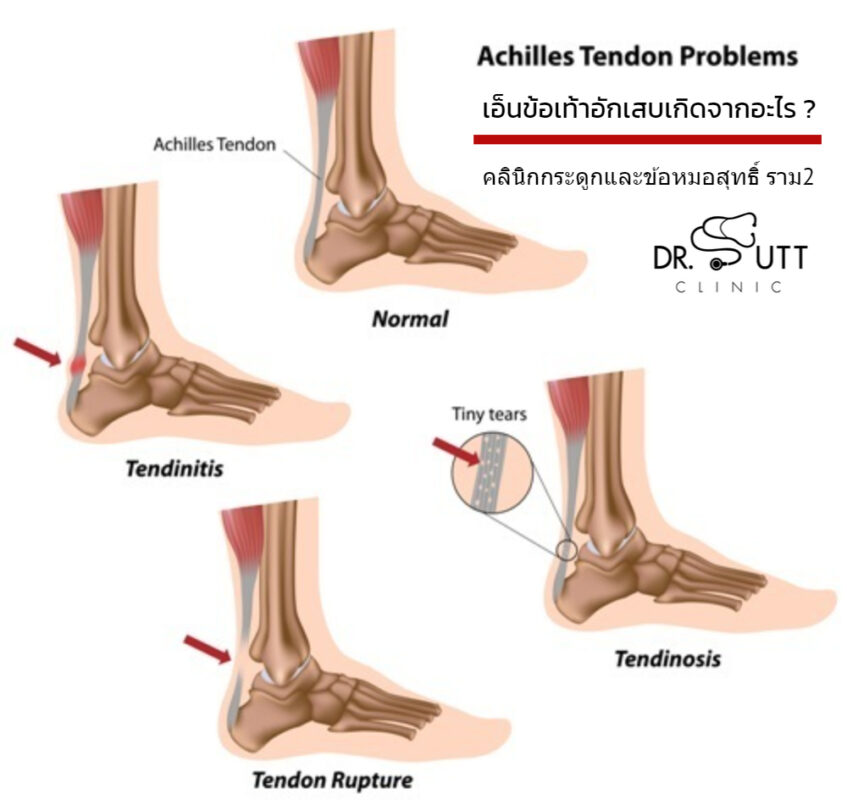

วิ่งแล้วเจ็บเอ็นร้อยหวายเป็นอะไรกันแน่… – หัวมุม #วิ่งเพื่อสุข | فيسبوك เอ็นข้อเท้าอักเสบเกิดจากอะไร ? – คลินิกกระดูกและข้อ (หมอสุทธิ์)

เอ็นข้อเท้าอักเสบเกิดจากอะไร ? – คลินิกกระดูกและข้อ (หมอสุทธิ์) ท่าบริหารเอ็นร้อยหวาย แก้เอ็นร้อยหวายตึง เอ็นร้อยหวายอักเสบ เอ็นร้อยหวายบวม